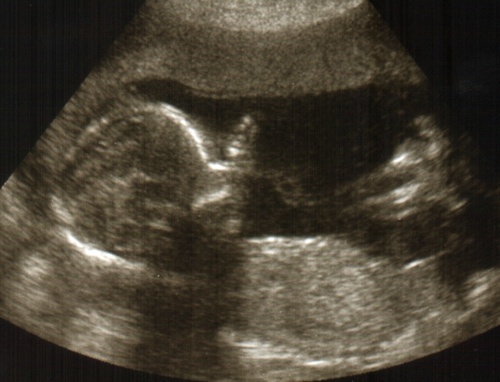

17+4 -es pocak

Kép

Sütike, boldog névnapot! Nagyon szép a pocid, ha nem tudnám, hogy két babóca van, nem is gondolnám, alig híztál?! Mi a titkod?